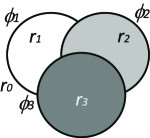

In the continuous domain, Vese and Chan (2002) extended their level set-based method to multiphase level sets. To segment objects, their method needs level set functions. The number of regions is upper-bounded by a power of two (Figure 12(a)). ¡ltx:note¿Therefore, the actual number of regions the method yields is sometimes not clear as it depends on the image and the regularization weights. This issue happens specifically when the number of regions of interest is less than .¡/ltx:note¿ Mansouri et al. (2006) proposed to assign an individual level set function to each object of interest (excluding the background), i.e. their method needs non-overlapping level set functions to segment objects (Figure 12(b)). Chung and Vese (2009) proposed another method that uses a single level set function for multi-object segmentation. They proposed to use different layers (or levels) of a level set function to represent different regions as opposed to just using the zero level set (Figure 12(c)). None of the aforementioned continuous methods guarantee a globally optimal solution for multi-label problems. Pock et al. (2008) proposed a spatially continuous formulation of Ishikawa’s multi-label problem. In their method, the non-convex variational problem is reformulated as a convex variational problem via a technique they called functional lifting. They used the following energy functional